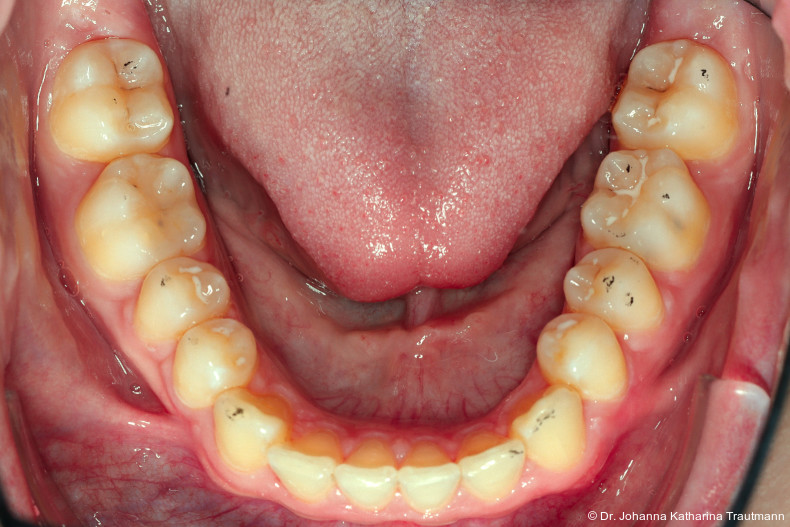

Nach transversaler Nachentwicklung der Maxilla mittels GNE nach Veltri wurde der Zahn 23 geschlossen freigelegt und an einem individualisier ten TPA nach distal angebunden. Zur Aufrichtung der Front und Mesialisierung des hypoplastischen Zahnes 22 kam zusätzlich eine 2x3Mechanik zum Einsatz. Eine rein translatorische Bewegung eines Zahnes ist auch mit einer festsitzenden Apparatur schwer zu erreichen, da der Kraftansatzpunkt nicht identisch mit dem Widerstandszentrum des Zahnes ist.7 Diese Problematik kann einerseits durch das Einbringen eines Versetzungsmomentes adressiert werden, andererseits durch eine Verlagerung des Kraftansatzpunktes. Angelehnt an den von Hong et al. beschriebenen Power Arm 8 wurde hierfür palatinal an Zahn 22 ein cranial gerichteter Hook angebracht (Abb. 3). Da Zahn 22 aufgrund seiner Hypoplasie eine verkürzte Wurzel aufwies, konnte so die Distanz zwischen Widerstandszentrum und Kraftangriffspunkt effizient reduziert werden. Eine weitere biomechanische Schwierigkeit stellte das geringe Alveolarknochenangebot im Spalt bereich mesial von 22 dar. In Bereichen mit Knochendefizit verschiebt sich das Widerstandszentrum nach apikal und wie in diesem Fall zusätzlich nach distal.9, 10 Um dem erhöhten Risiko für Kipp bewegungen entgegenzuwirken, muss hier besonders auf die Steuerung des M/F-Quotienten geachtet werden. Der vestibulär durchgebrochene Zahn 13 benötigte keine Freilegung. Um seine korrekte Einstellung zu ermöglichen, wurde die Mesialwanderung des Zahnes 16 mithilfe des TPAs korrigiert sowie eine Mittellinienkorrektur nach links mittels 2x3 Mechanik durchgeführt.

Nach etwa zwei Jahren initialer Behandlung konnte nach abgeschlossenem Wurzelwachstum aller bleibenden Zähne (mit Ausnahme der Weisheitszähne) mit der Hauptbehandlung unter Verwendung einer vollständigen Multibracketapparatur von 7 bis 7 im Ober und Unterkiefer begonnen werden. Die vergleichsweise lange Vorbehandlung erscheint zwar auf den ersten Blick behandlungszeitverlängernd, sorgt jedoch für eine deutlich bessere Mundhygienefähigkeit sowie für eine Reduktion des apparativen Aufwandes und der biomechanischen Komplexität in der Hauptbehandlungsphase. Diese Faktoren stehen in engem Zusammenhang mit Patientenkomfort und Motivation.